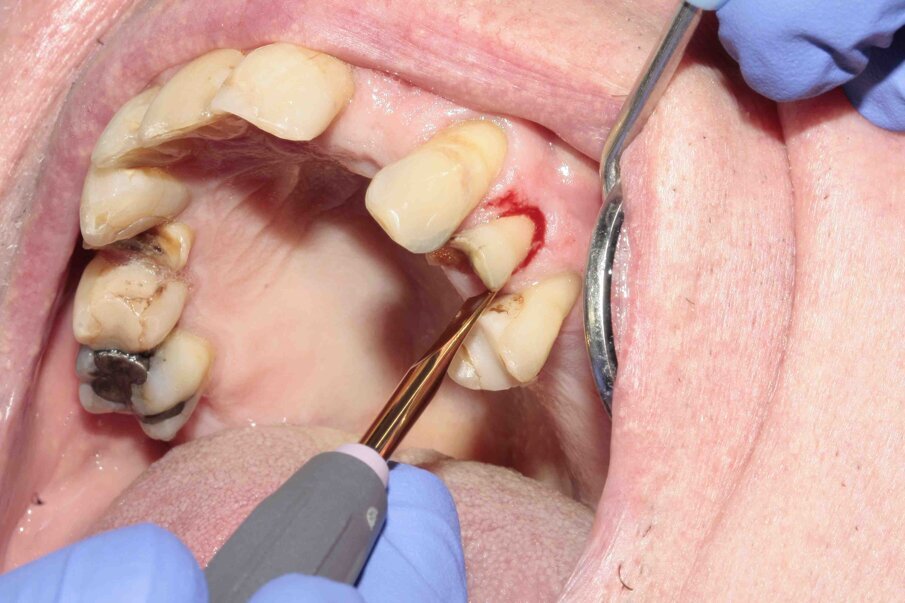

A 70-year-old female patient visited our clinic owing to a fractured maxillary first molar. Tooth #24 had previously had a large composite restoration that was no longer in place at the time of the dental appointment.

Tooth #24 was severely decayed down to the marginal bone edge.

Figs. 2–4: The tooth was luxated with Luxator P4 (dual edge, lilac).

Figs. 5–7: Luxation was continued with Luxator P1 (straight blade, dark green).